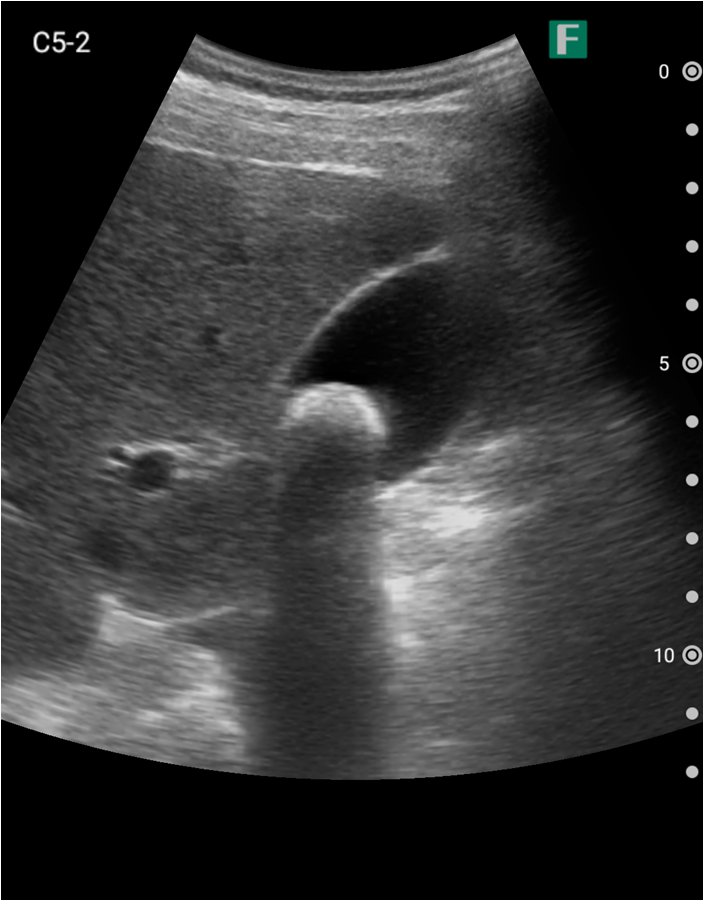

夜間、腹痛を主訴に高齢の男性が救急外来にいらっしゃいました。その方は尿道カテーテルが入っており、頻繁にカテーテルの閉塞を起こしている病歴がありました。

視診を行い下腹部に軽度の膨隆が確認できましたが体外から出ているカテーテルには明らかな閉塞を認めませんでした。そこで、iViz airで観察したところ、膀胱内に約400mlの残尿を認めカテーテル閉塞による腎後性腎不全と診断を確定させることができました。尿道カテーテルを抜去した際、外見からは見えないカテーテルの先端部分に沈殿物を認め、閉塞の原因であるとわかりました。その後尿道カテーテルの交換を行うと残尿の排出ともに腹痛は消失し、無事に帰宅されました。iViz airでの観察が尿閉の確定診断につながった症例です。